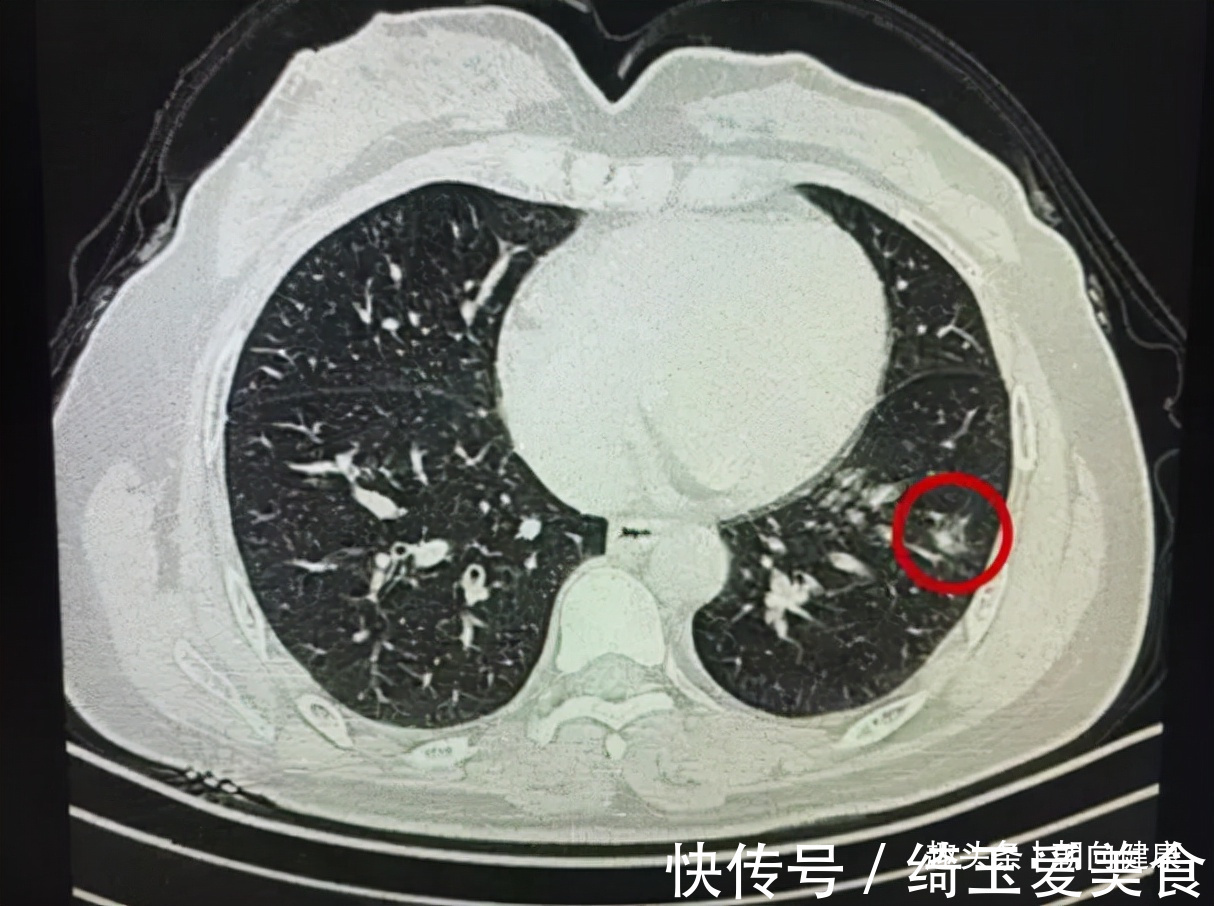

人吃五谷杂粮,哪能不生病?如今各种新型病频发,尤其是癌症就像是感冒一般,所以人们的体检意识也越来越强,有一些人每年都会定期做体检,这样可以做到早发现早治疗,预防大病的产生,大大增加治愈率。近几年来,很多人在体检的时候查出患有结节的现象。比如出现了甲状腺结节,肺结节,乳腺结节等等,有一些人以为自己出现了结节,就是患上了癌症,其实大多数体检时查出的结节都是良性的,大家首先不要惊慌,还要谨遵医嘱进一步随访。